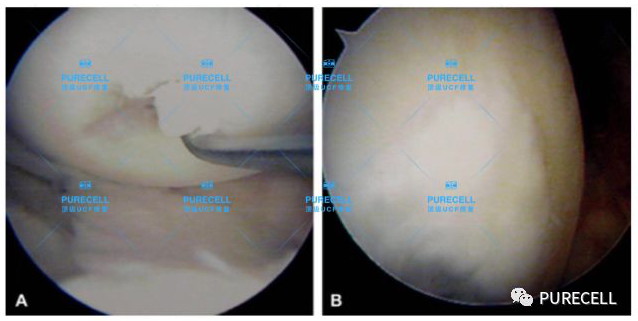

PURECELL首席科學家以及運動醫療專家已經驗證了UCF對膝關節修復的有效性,下圖是UCF軟骨及半月板修復前後影像對比。

UCF膝關節修復的主要原理是通過UCF成分,改善膝關節內環境,有效激活幹細胞靶向修復膝關節組織,修復韌帶損傷、半月板損傷,修復軟骨及髕骨等組織,能有效減少軟骨受損、骨刺等所帶來的疼痛,並且有效避免了軟骨半月板等膝關節組織的持續磨損和惡化,從根源上改善膝關節疼痛等問題給生活帶來的困擾。